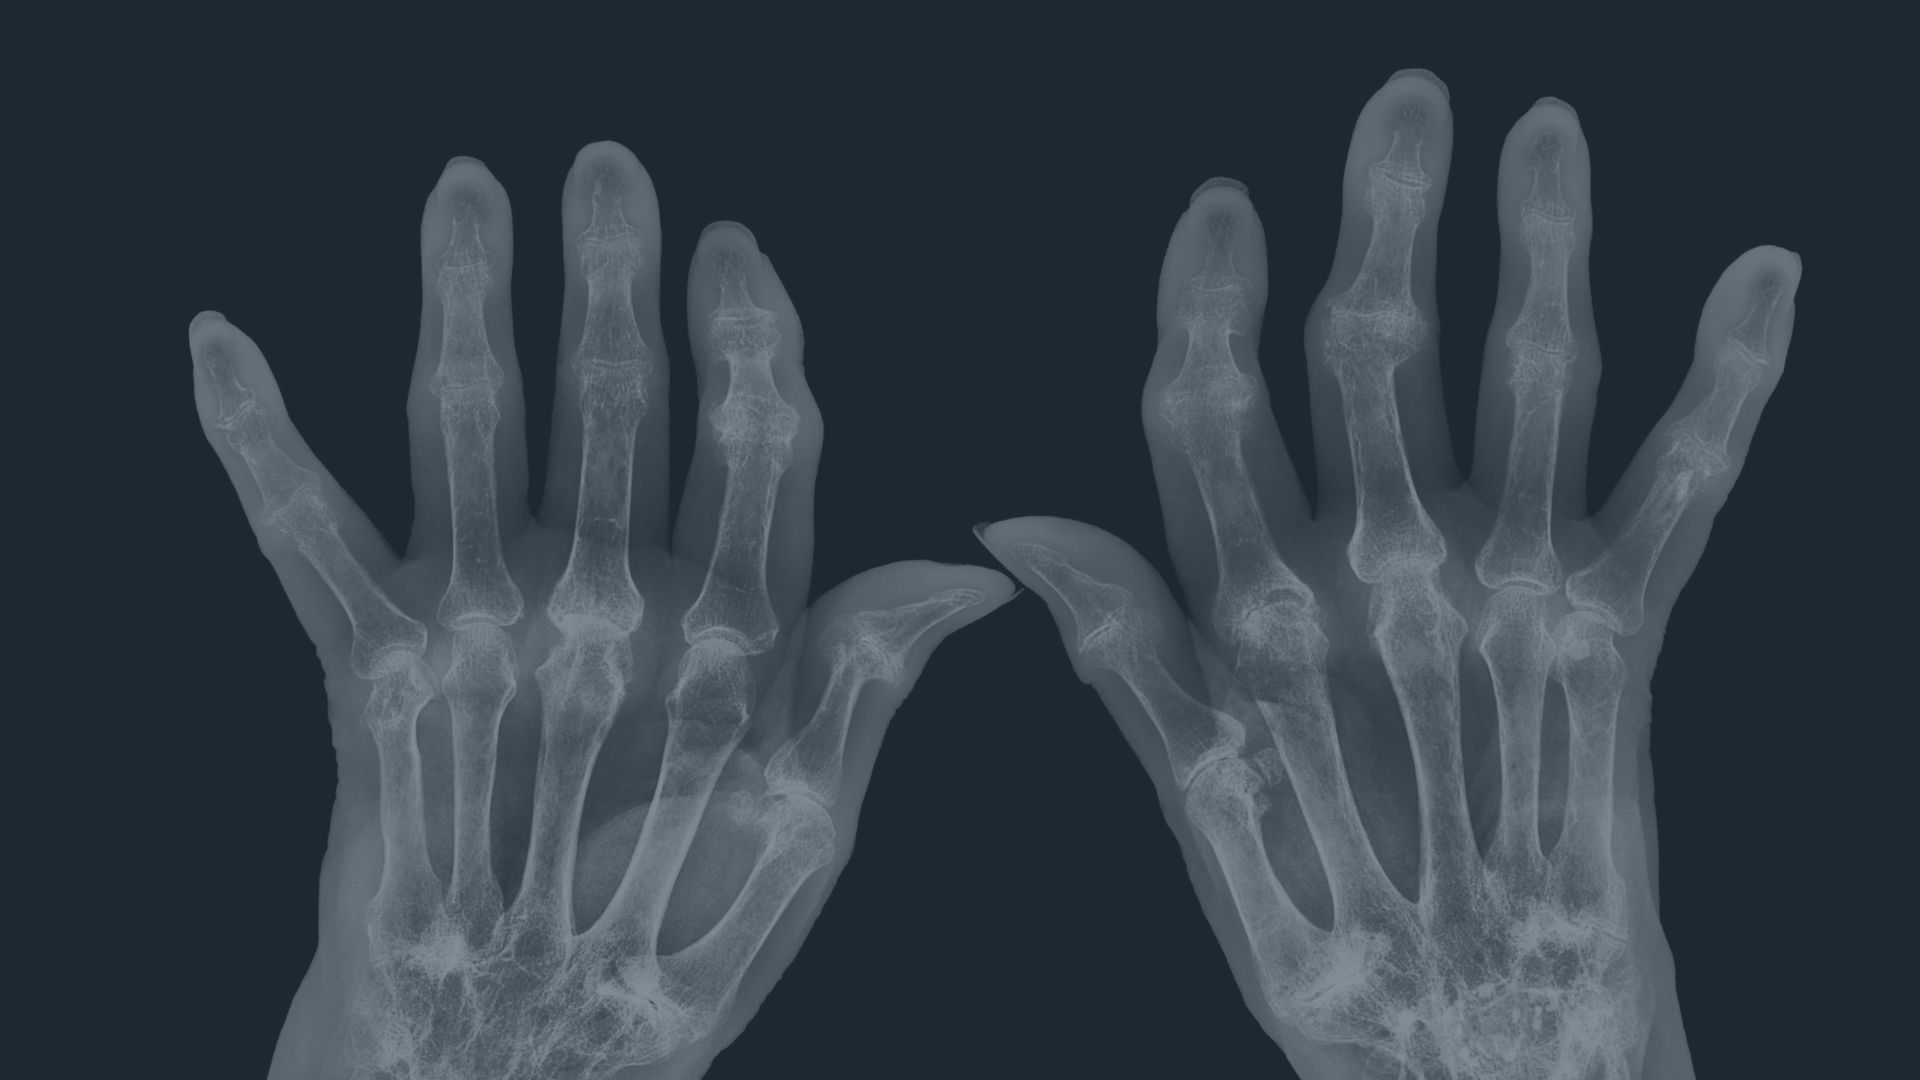

Inflammation, Autoimmunity & Joint Pain

Discover how immune dysregulation affects joints, why and how inflammation drives pain, and how dietary patterns influence symptom control.

Learn More About This